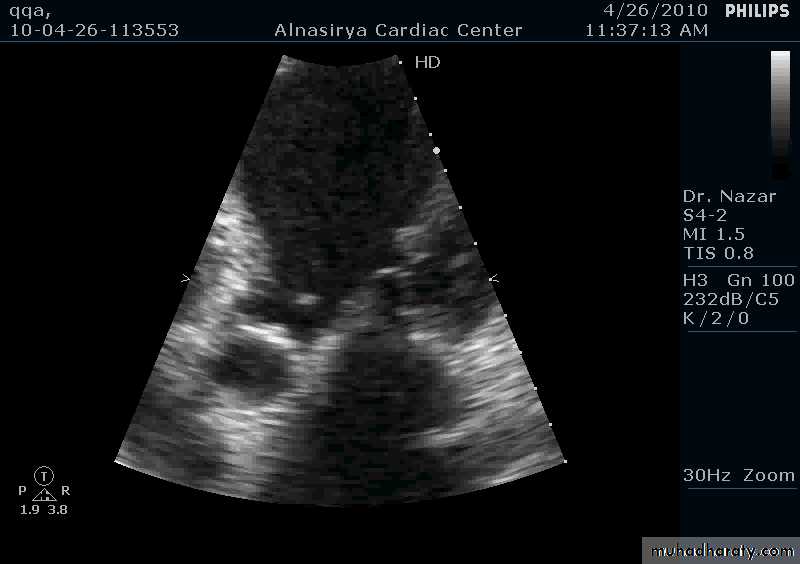

Vegatations on the aortic valve

35

VEGETATIONS

36

37